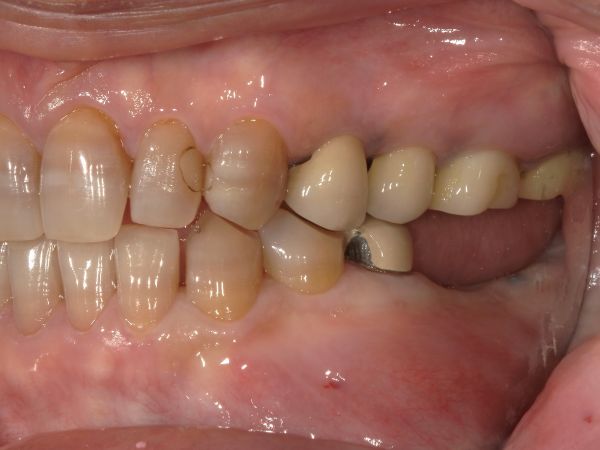

お口の中の状態の写真がこちらになります。

右下の6番目と7番目の歯には歯茎にフィステルという出来物がありました。

フィステルは右下6番目と7番目の根管治療(根の治療)の不備によって生じた膿の出口になります。

また、被せ物と歯茎の隙間に大きな虫歯があることも分かるかと思います。こちらの矢印が虫歯です。

被せ物を外して根管治療を行うこととしましたが、被せ物を実際に外して虫歯を削っていくと、かなり自分の歯の残量が少なくなってしまいました。ある程度の歯が残っていないと、被せ物をしたとしてもすぐに虫歯になってしまったり、被せ物が外れてすぐトラブルを起こしてしまいます。